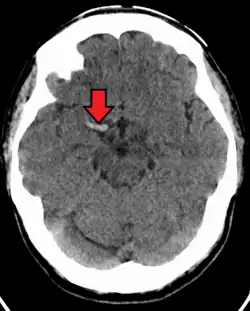

Cerebral venous sinus thrombosis (CVST) is a rare form of stroke which results from the blockage of the dural venous sinuses by a thrombus. Symptoms may include headache, abnormal vision, any of the symptoms of stroke such as weakness of the face and limbs on one side of the body and seizures. The diagnosis is usually made with a CT or MRI scan. The majority of persons affected make a full recovery. The mortality rate is 4.3%.[15]